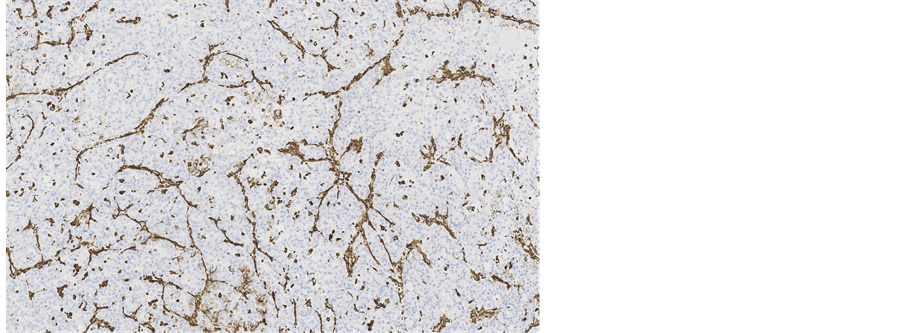

Immunohistochemical staining showed, that the tumour cells were diffusely positive for monoclonal antibodies against pancytokeratin (AE1/AE3) (Figure 5), cytokeratin 7 was positive in 5% of tumour cells (Figure 6), other markers, which showed immunoreactivity: EMA (5%), RCC-smp314 (30%), CA-125 (30%), p53 (was expressed weakly) (Figure 7), AMACR (diffuse positivity), CD10 (50%), Cyclin D1 (40% - 50%) and bcl-2. The tumour cells were negative for Vimentin (Figure 8), WT1 (Figure 9), Cytokeratin 20, ER/PR, CEA (Figure 10), TTF-1, CD57.

Figure 5. Microscopic appearance of the endometrial tissue from curetting specimen-clear cell carcinoma, immunohistochemical staining with monoclonal antibodies against pancytokeratins AE1/AE3, ×10.